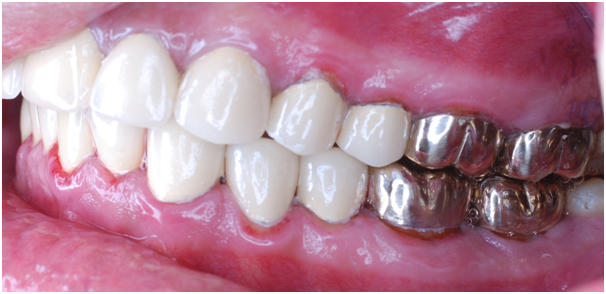

Figure 18 Post op left side.

Esthetic, phonetics and occlusion were checked after cementation the temporary crowns with temporary (Pro. Temp) luting agent. To avoid any functional problems, the patient was instructed to give the temporaries a period of trial for 2 weeks. Intra occlusal relationship was repeated at this stage again. When the patient reported no discomfort, the final crowns were constructed. Final crowns were cemented using resin composite (Rely X Unicem) luting agent. Teeth restored were # 2, 3, 4, 5, 6, 7, 8, 9,10, 11, 12, 13, 14, 15,18, 19, 20, 21, 22, 23, 24, 25, 26, 27, 28, 29, 30 and 31. Postoperative pictures, x-rays, and impressions were taken (Figure 9−19). The case had a good prognosis considering the patient, good general health and proper attitude toward his oral hinging reported during the maintenance and treatment phases. The periodontium is in functional health status, using gold alloys to restore posterior teeth as well as porcelain-fused to metal crowns to restore anterior teeth conserve tooth structures by minimizing the amount of tooth structure to be cut.